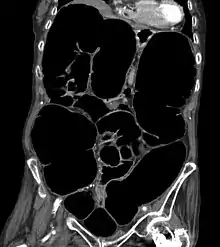

CT-Scan showing a Cross-section of the abdomen of an elderly lady with an IPO. - CT scans